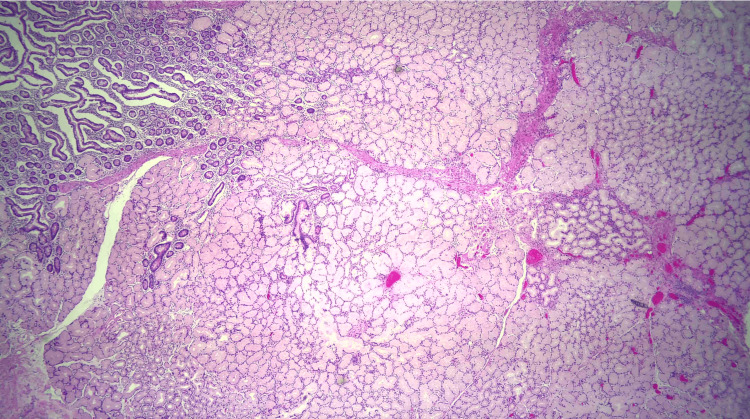

Due to the patient’s symptoms, risk factors, and degree of obstruction, these findings were concerning for possible metastasis. Both gastroenterology and general surgery were consulted for consideration of either endoscopic ultrasound with fine-needle aspiration or open surgical biopsy of the mass. Ultimately after multidisciplinary discussion, general surgery was planned for a biopsy of the mass and management with PD. Pathology revealed Brunner gland hyperplasia, pseudocysts with granulation tissue, chronic inflammation, and proteinaceous material consistent with GP (Figures 6–8). MRI of the liver deemed the lesion to be a benign hemangioma. Additionally, cluster of differentiation 31 (CD31), human herpesvirus-8 (HHV-8), and Helicobacter pylori immunostaining were all negative. He did well postoperatively and was discharged with bilateral Jackson-Pratt drains. At his outpatient follow-up, he endorsed improvement in appetite and resolution of his symptoms.